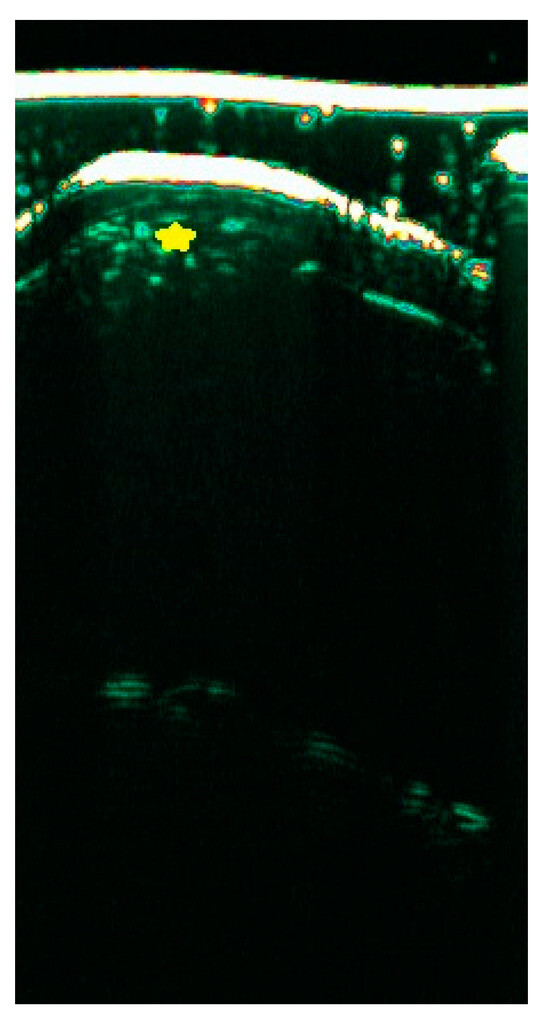

In recent years, ultrasound imaging technology has been widely used and has played an increasingly important role in diagnosing and treating skin diseases, providing a large amount of key visual information in order to meet the challenges of complex skin diseases. Skin ultrasound imaging is a new technology category that is clinically widely endorsed. In this context, the large-scale application of ultrasound in skin diseases has gradually gained attention. In this regard, we would like to set up a new Special Issue on applying ultrasound imaging technology in skin diseases and focus on publishing some of the latest, high-quality, and excellent clinical research.